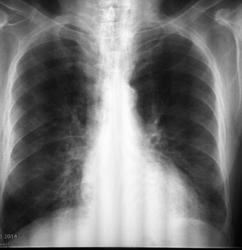

М., 71г., выявлен по флюорографии, направлен с д-зом: ХНЗЛ, плевропневмония слева. Госпитализирован с ХОБЛ, обострение. Клинически - не лихорадит, одышка, кашель, кровохарканье. Выполнена ФБС: картина атрофич. эндобронхита. Пришел на контроль.

конечно, смотреть сложно в повернутом виде, поэтому можно только предположить, но я согласна с Вами, что здесь нельзя исключить центральный с-ч, даже при наличии отрицательных данных ФБС - широкий левый корень, расширенное верхнее средостение и гиповентиляция в нижней доле слева. Поэтому, рекомендую КТ и консультацию онколога повторно.

Присоединяюсь-цикличность левого корня и гиповентиляция верхнего сегмента нижней доли.КТ поставит точку

Динамика отрицательная.Впечатление о нижнедолевой пневмонии слева, осложнённой гиповентиляцией. Так что и рак - не исключён, с параканкрозным пневмонитом

Опухоль нужно искать, нижняя доля слева в гиповентияции, средостение влево уезжает, это не пневмония

Уважаемые коллеги, спасибо за помощь! С 31.03. по 7.04. Лечили аугментином, амброксолом, сальбутамолом и т.д. Клинически больному не хуже, пришел на контроль перед выпиской. Рекомендовала КТ для исключения центрального преимущественно эндобронхиального рака нижней доли левого легкого, осложненного гиповентиляцией S6,10. КТ сделали, заключение: пневмония в нижней доле левого легкого, ст. разрешения. Бронхоэктазы. Пуль монологи довольны, больной выписан.

КТ нужно было делать до ФБС. А после нее они получили картину кровоизлияний и расценили как пневмонию. Это -мое предположение, но то, что уже "кровило" во время проведения ФБС, -еще один аргумент за "зло".В заключении бронхоскопии об этом должно быть написано.Так что -прямая дорога к онкологам и вы правы, что заподозрили рак.